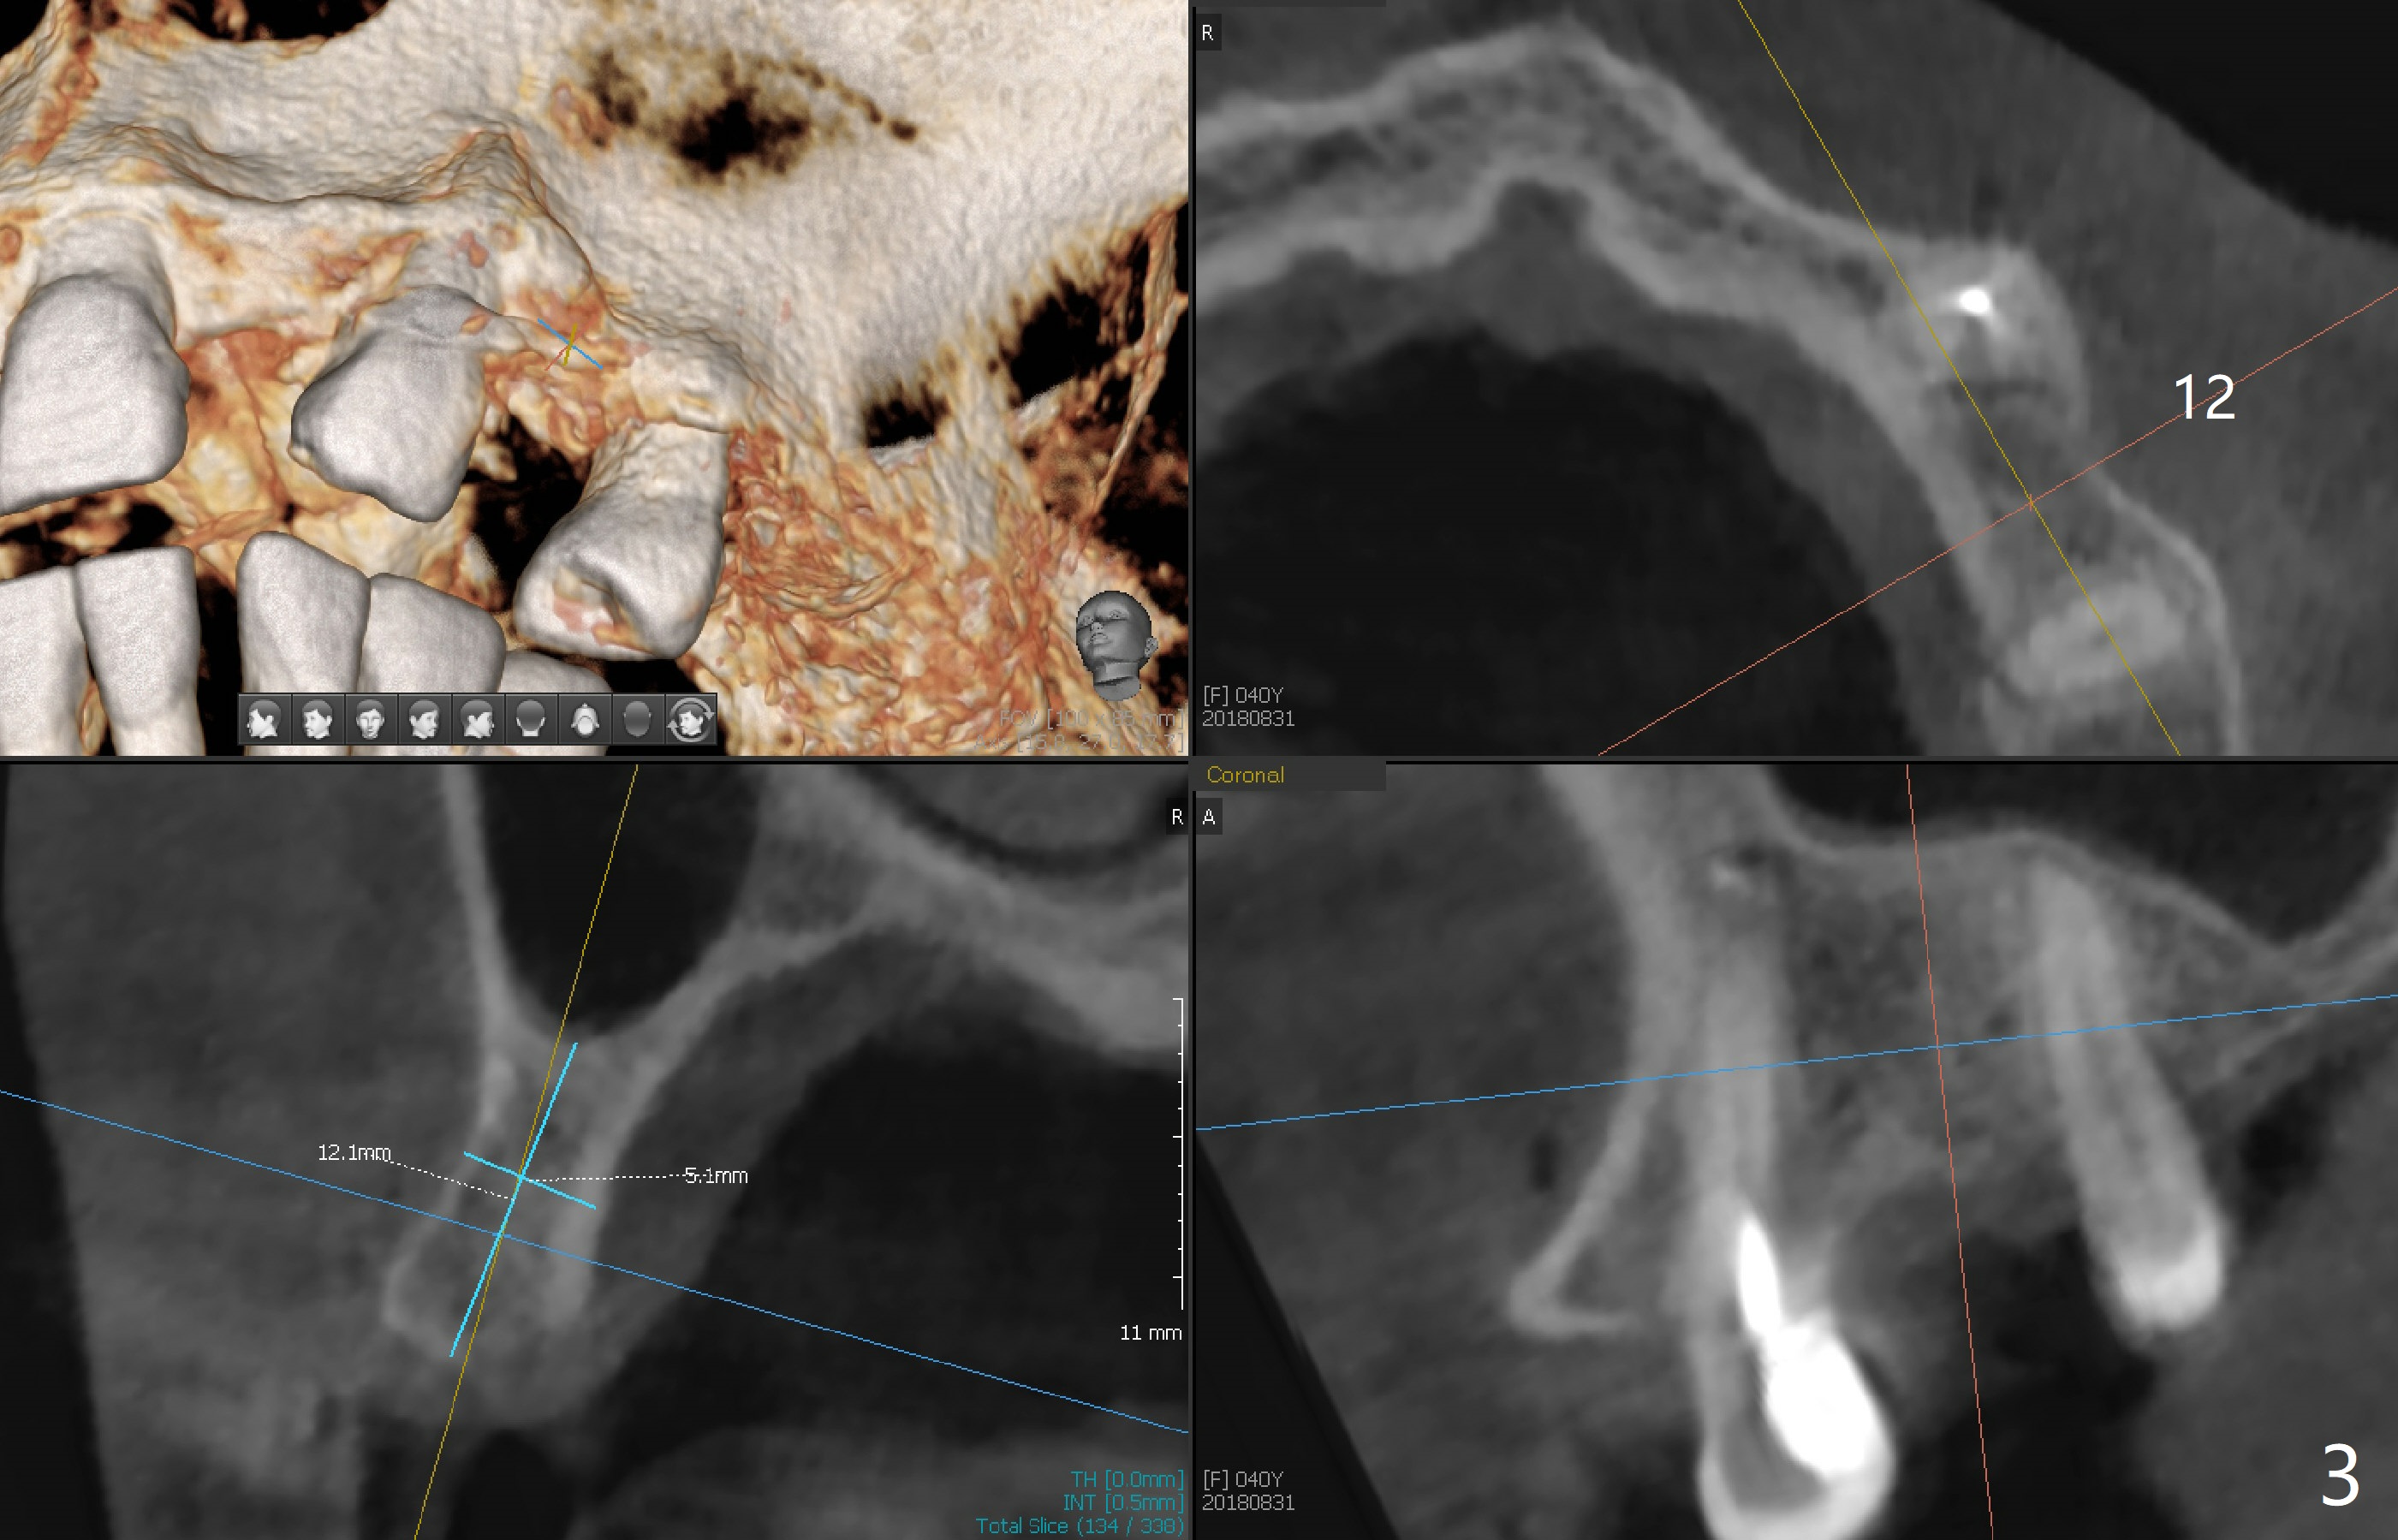

After cementation of implant crowns of #4 and 5, a  40-year-old skinny woman requests implants at #10 and 12 (Fig.1).  Since the ridge is narrow (Fig.2,3), narrow implants are required (2x12 and 3x10 mm).  As malpositioned implants at #4 and 5 were placed with free hand, guide is imminent for the new implants.